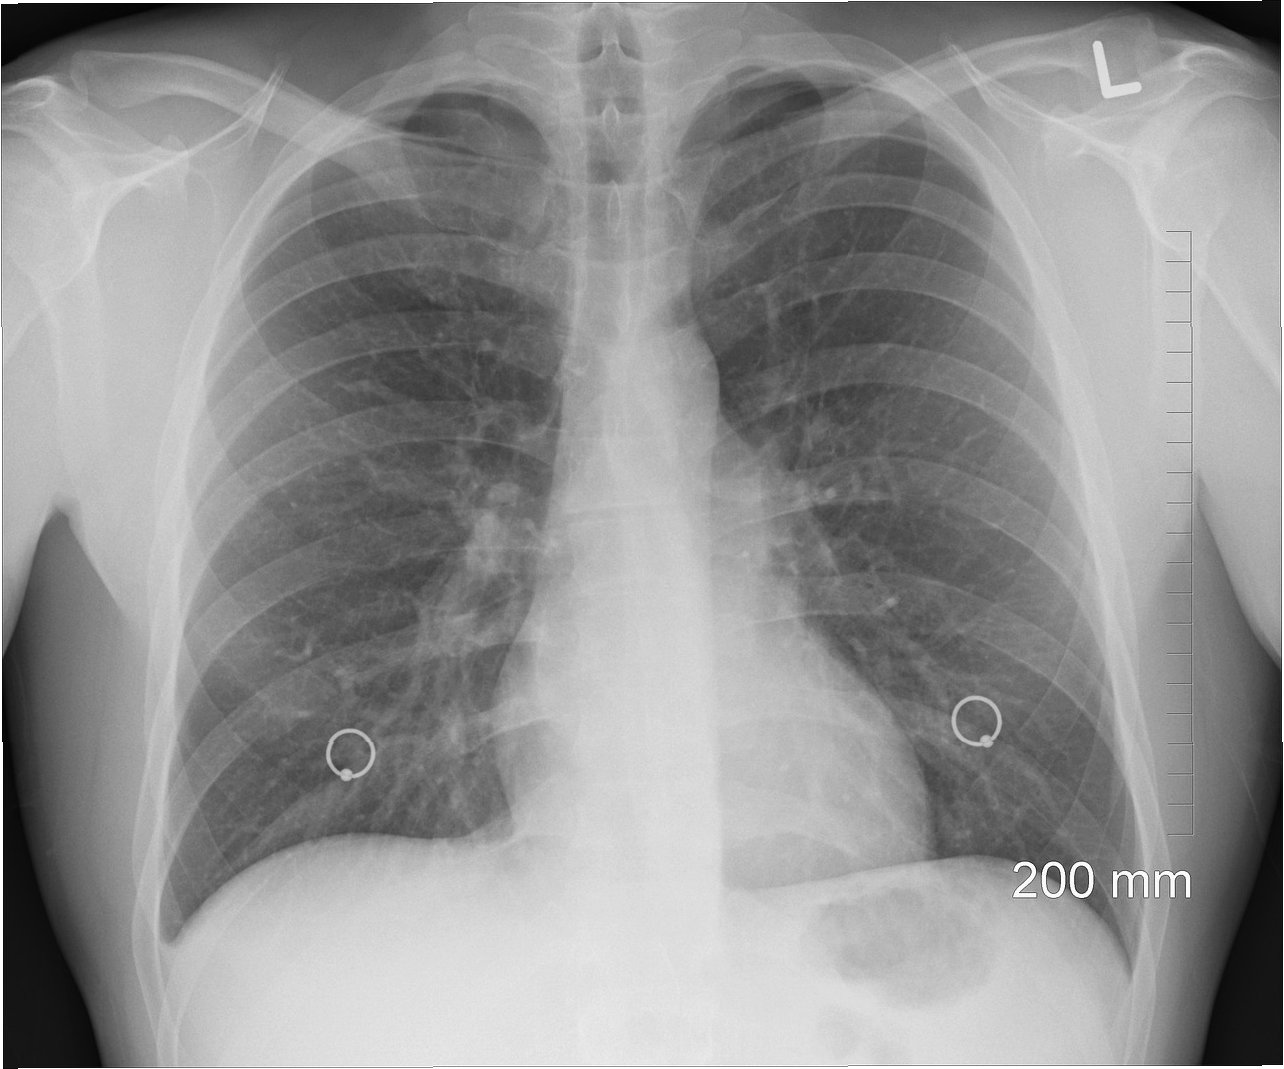

한의사의 엑스레이(X-ray) 사용을 가능하게 하는 법안을 두고 의사와 한의사 사이의 갈등이 격화하고 있습니다의사단체는 "한의사의 엑스레이 사용은 과학적 검증과 전문성이 없어 위험하다"며 거세게 반발하는 반면, 한의사들은 "시대착오적인 직역 이기주의"라며 맞서고 있습니다.

한의사의 엑스레이 사용을 허용하는 의료법 개정안은 진단용 방사선 발생장치의 안전관리책임자에 대한 규정을 바꾸는 내용이 골자입니다. 현행 의료법은 의료기관 개설자 등이 방사선 장치를 설치할 경우 보건복지부령에 따라 안전관리책임자를 선임하도록 하고 있으며, 안전관리책임자의 자격은 의사, 치과의사, 방사선사 등으로 제한하고 있습니다.

이에 대해 의협은 "국민 건강과 생명을 혼란에 빠뜨리는 치명적인 도발"이라고 일갈했습니다. 김택우 의협 회장은 "의료법에 따라 한의사는 한방 의료행위만 할 수 있고, 한의사의 엑스레이 사용은 명백히 무면허 의료행위에 해당한다"며 "엑스레이는 고도의 전문성과 해부학적 지식이 있어야 하는 의료장비인 데다 방사선 차폐시설과 영상의학과 기사 등을 확보해야 한다"고 지적했습니다.